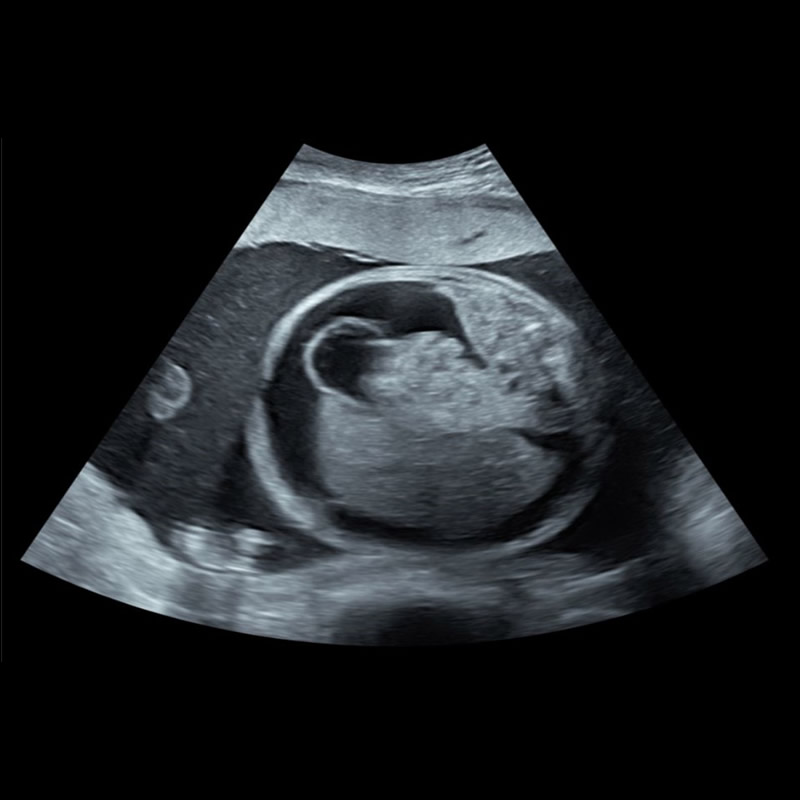

Embarazo de 26,2 semanas. MC Genitorragia